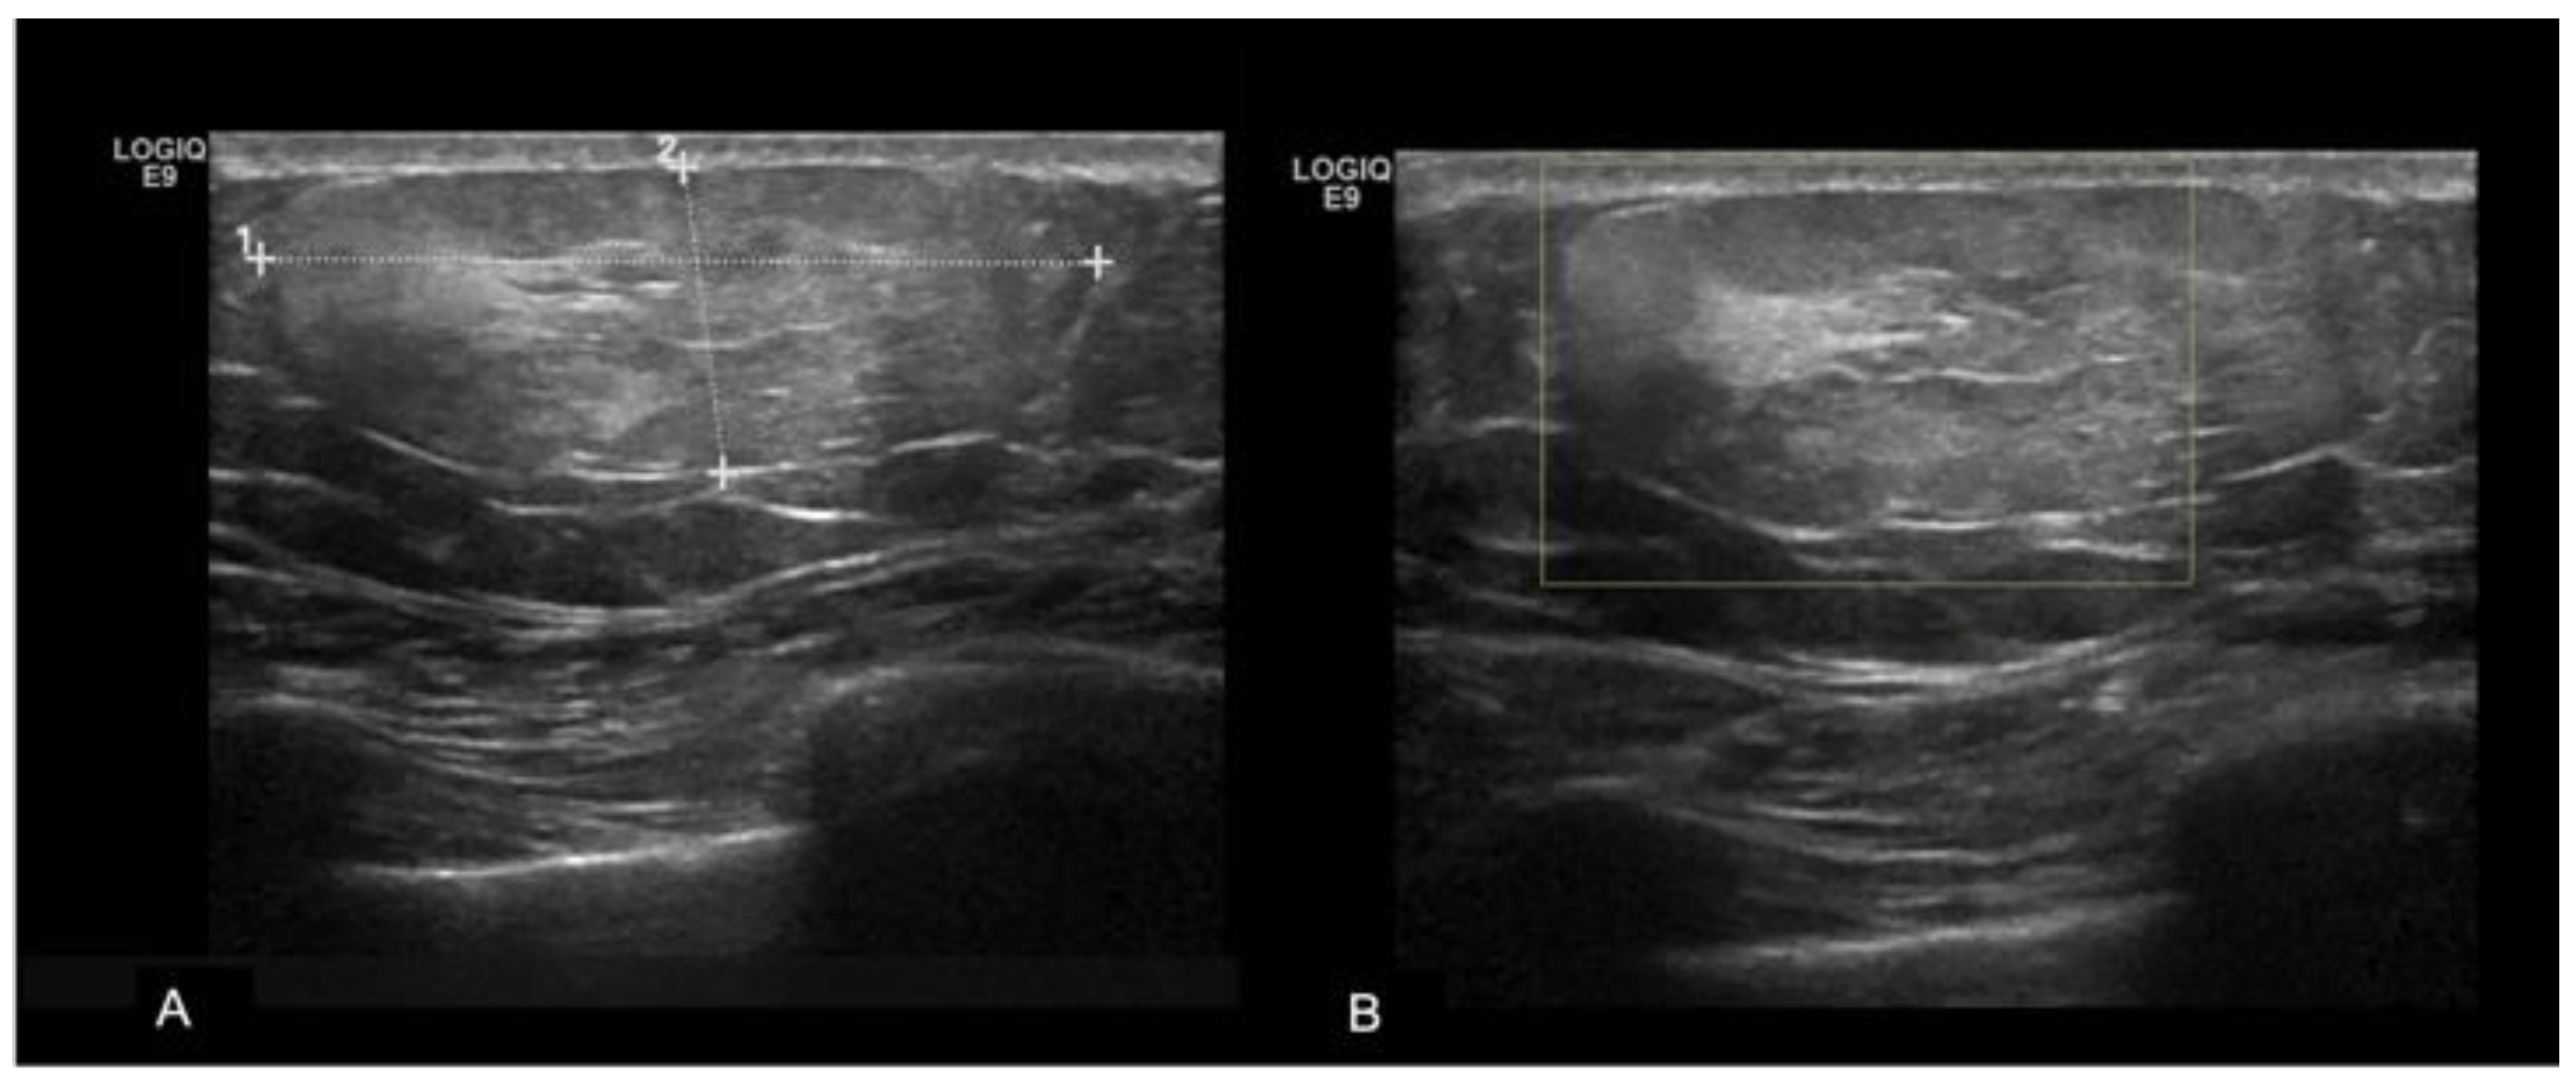

Lipomas, the second most common benign lesions in the MB, are composed of adipose tissue and typically present as soft, mobile, and palpable masses in clinical examination. However, they are frequently detected incidentally. Mammographically, lipomas appear as well-defined radiolucent oval masses with a radiopaque capsule that might be difficult to detect [14,15]. On ultrasound, lipomas demonstrate an oval shape, parallel orientation, iso-hyperechoic echogenicity, and lack detectable vascular flow [16] (Figure 3).

Figure 3.

A 35-year-old men with a palpable lump in the inner quadrants of the left breast. On a B-mode (A) breast ultrasound, there is an oval shaped and hyperechoic mass, with circumscribed margins and parallel orientation. No posterior feature is associated. On color-doppler (B), there are no signs of vascularization. The imaging features are consistent with a lipoma.